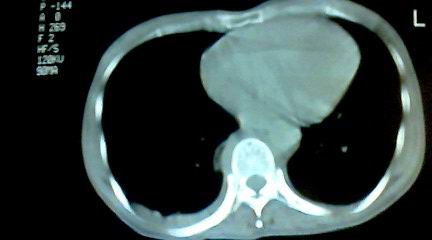

标题: CT25218:请教!胸部CT,胸8椎体骨质破坏,伴周围软组织肿。 [打印本页]

标题: CT25218:请教!胸部CT,胸8椎体骨质破坏,伴周围软组织肿。

患者,女41岁,肢体乏力。

两肺上叶继发性肺结核;胸椎结核并椎旁寒性脓肿形成。

胸椎结核并椎旁寒性脓肿形成。